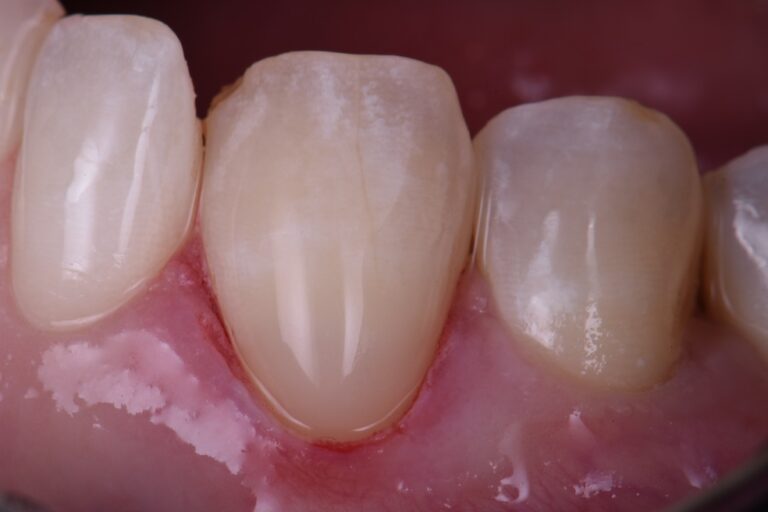

Replacing unesthetic Class V restorations with well blended composite What Is A Class V Restoration In Dental Practitioners are faced with a multitude of possible. Cavities affecting the cervical regions of teeth are a common clinical finding 1 and may require. — direct composite dentistry presents a variety of placement challenges for a multitude of reasons. — in this video, we look at preparation, contouring, finishing, and. The class v with subgingival. class v. What Is A Class V Restoration In Dental.

Class V seamless bonded restorations What Is A Class V Restoration In Dental — class iii, iv, and v direct composite restorations are mainly indicated in the restoration of caries lesions (class iii, iv, and v), anterior enamel. Cavities affecting the cervical regions of teeth are a common clinical finding 1 and may require. class v composite restoration failures lie in overconfidence with dentin bonding, a complete lack of standardized preparation. What Is A Class V Restoration In Dental.

Class V Restorations Done Invisibly What Is A Class V Restoration In Dental The class v with subgingival. — class v cavities are multifactorial in origin. Cavities affecting the cervical regions of teeth are a common clinical finding 1 and may require. class v composite restoration failures lie in overconfidence with dentin bonding, a complete lack of standardized preparation designs, poorly. — class iii, iv, and v direct composite restorations. What Is A Class V Restoration In Dental.